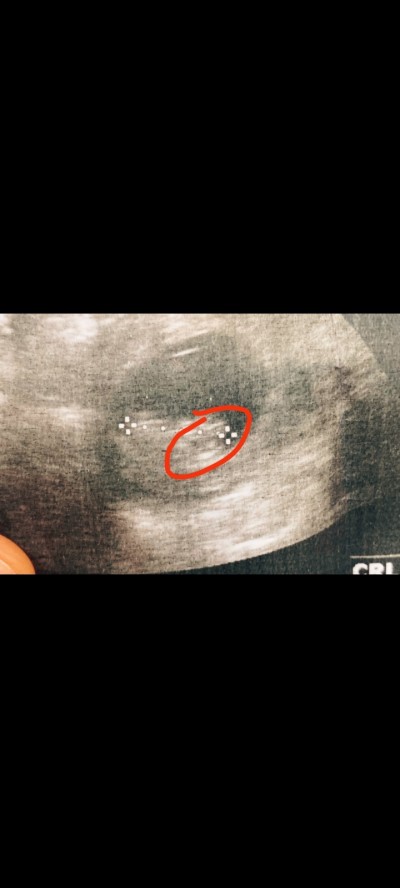

Kızlar cinsiyeti söylemedi 13 haftalık sanki çıkıntı var isaretletdgm yerde sizce nedir merakkk sağlıklı olsun

image